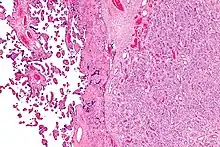

Placenta with an especially large 10cm chorioangioma |

Chorioangioma, or chorangioma, is a benign tumor of placenta. It is a hamartoma-like growth in the placenta consisting of blood vessels,[1] and is seen in approximately 0.5 to 1% pregnancies.[2] It is mostly diagnosed ultrasonically in the second trimester of pregnancy. Large chorioangiomas are known to cause complications in pregnancy, while the smaller ones are asymptomatic.

The origin of chorioangioma is from primitive chorionic mesenchyme. It develops when the blood vessels and stroma undergo rapid proliferation independent of the surrounding tissue. Based on histological features, chorioangioma is classified by Marchetti[5] into three types:[6]

- Cellular type : This type is immature and contains mostly cellular elements packed compactly.

- Angiomatous (vascular) type : This is the most common type of choriocarcinoma. It is distinguished by the presence of numerous small blood vessels.

- Degenerative type : This is the mature type with degenerative changes.

Each type is believed to represent a phase of tumor development. Chorioangioma has no malignant potential.

Histologically, chorioangiomas consist of abundant vascular channels and may be cellular.